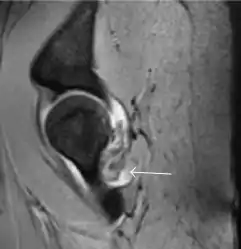

Most of the angles and measurements described in the plain radiograph section can be accurately reproduced on MRI. In addition, the superiority of MRI resolution with intra-articular contrast allows detection of labral and chondral abnormalities that may influence the choice of medical, percutaneous, or surgical management (Figure 9).[1]

Figure 9:

- Sagittal T1 weighted image showing anterosuperior labral tear.[1]

- Sagittal T1 weighted image showing chondral lesion.[1]

- Sagittal CT-arthrography showing posteroinferior chondral injury.[1]

- Coronal CT-arthrography (d) showing ligamentum teres tear.[1]

MR arthrography has proven superior in accuracy when compared to native MR imaging. It is considered the best technique to assess the labrum. Knowledge of the normal variable morphology of the labrum helps to differentiate tears from normal variants. A triangular shape is most commonly seen in 66% of asymptomatic volunteers, but round, flattened, and absent labra can also be found in asymptomatic populations. MR arthrography has demonstrated sensitivity over 90% and specificity close to 100% in detecting labral tears. Loose bodies are demonstrated as filling defects surrounded by the hyperintense gadolinium.[1]

Association between labral tears and chondral damage has been demonstrated. This underscores the interaction between cartilage and labrum damage in the progression of osteoarthritis. Chondral damage to the posteroinferior part of the acetabulum as a contrecoup lesion occurs in approximately one-third of pincer cases secondary to persistent abutment on the anterior part of the joint leading to a slight posteroinferior subluxation. This is considered a bad prognosis sign.[1]

MR arthrography can also demonstrate ligamentum teres rupture or capsular laxity, which are debated causes of microinstability of the hip. Elongation of the capsule or injury to the iliofemoral ligament or labrum may be secondary to microtrauma in athletes. MR can demonstrate abnormalities in these cases, such as increased joint volume or a ligamentum teres tear (Figure 9).[1]